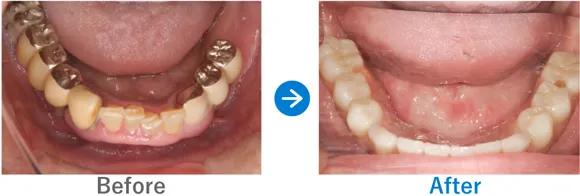

全顎上下共にブリッジ治療されている。重度の歯周病で歯がグラグラしている。

上下、ALLON4

治療結果

上下のALLON4を実施して治療同日に上下手術を行った。治療後すぐに仮歯が入ったので、とても喜んでいただいた。治療終了。メンテナンス来院継続中。

現在、セルフケアもしっかりされていて、メンテナンスも欠かさず来院していただいているため、インプラントは問題なく使えています。先日、横浜院で10年ぶりくらいにお会いしたのでご挨拶したら、とても喜んでくださりました。あの時インプラントの決断をして良かったと仰っていました。